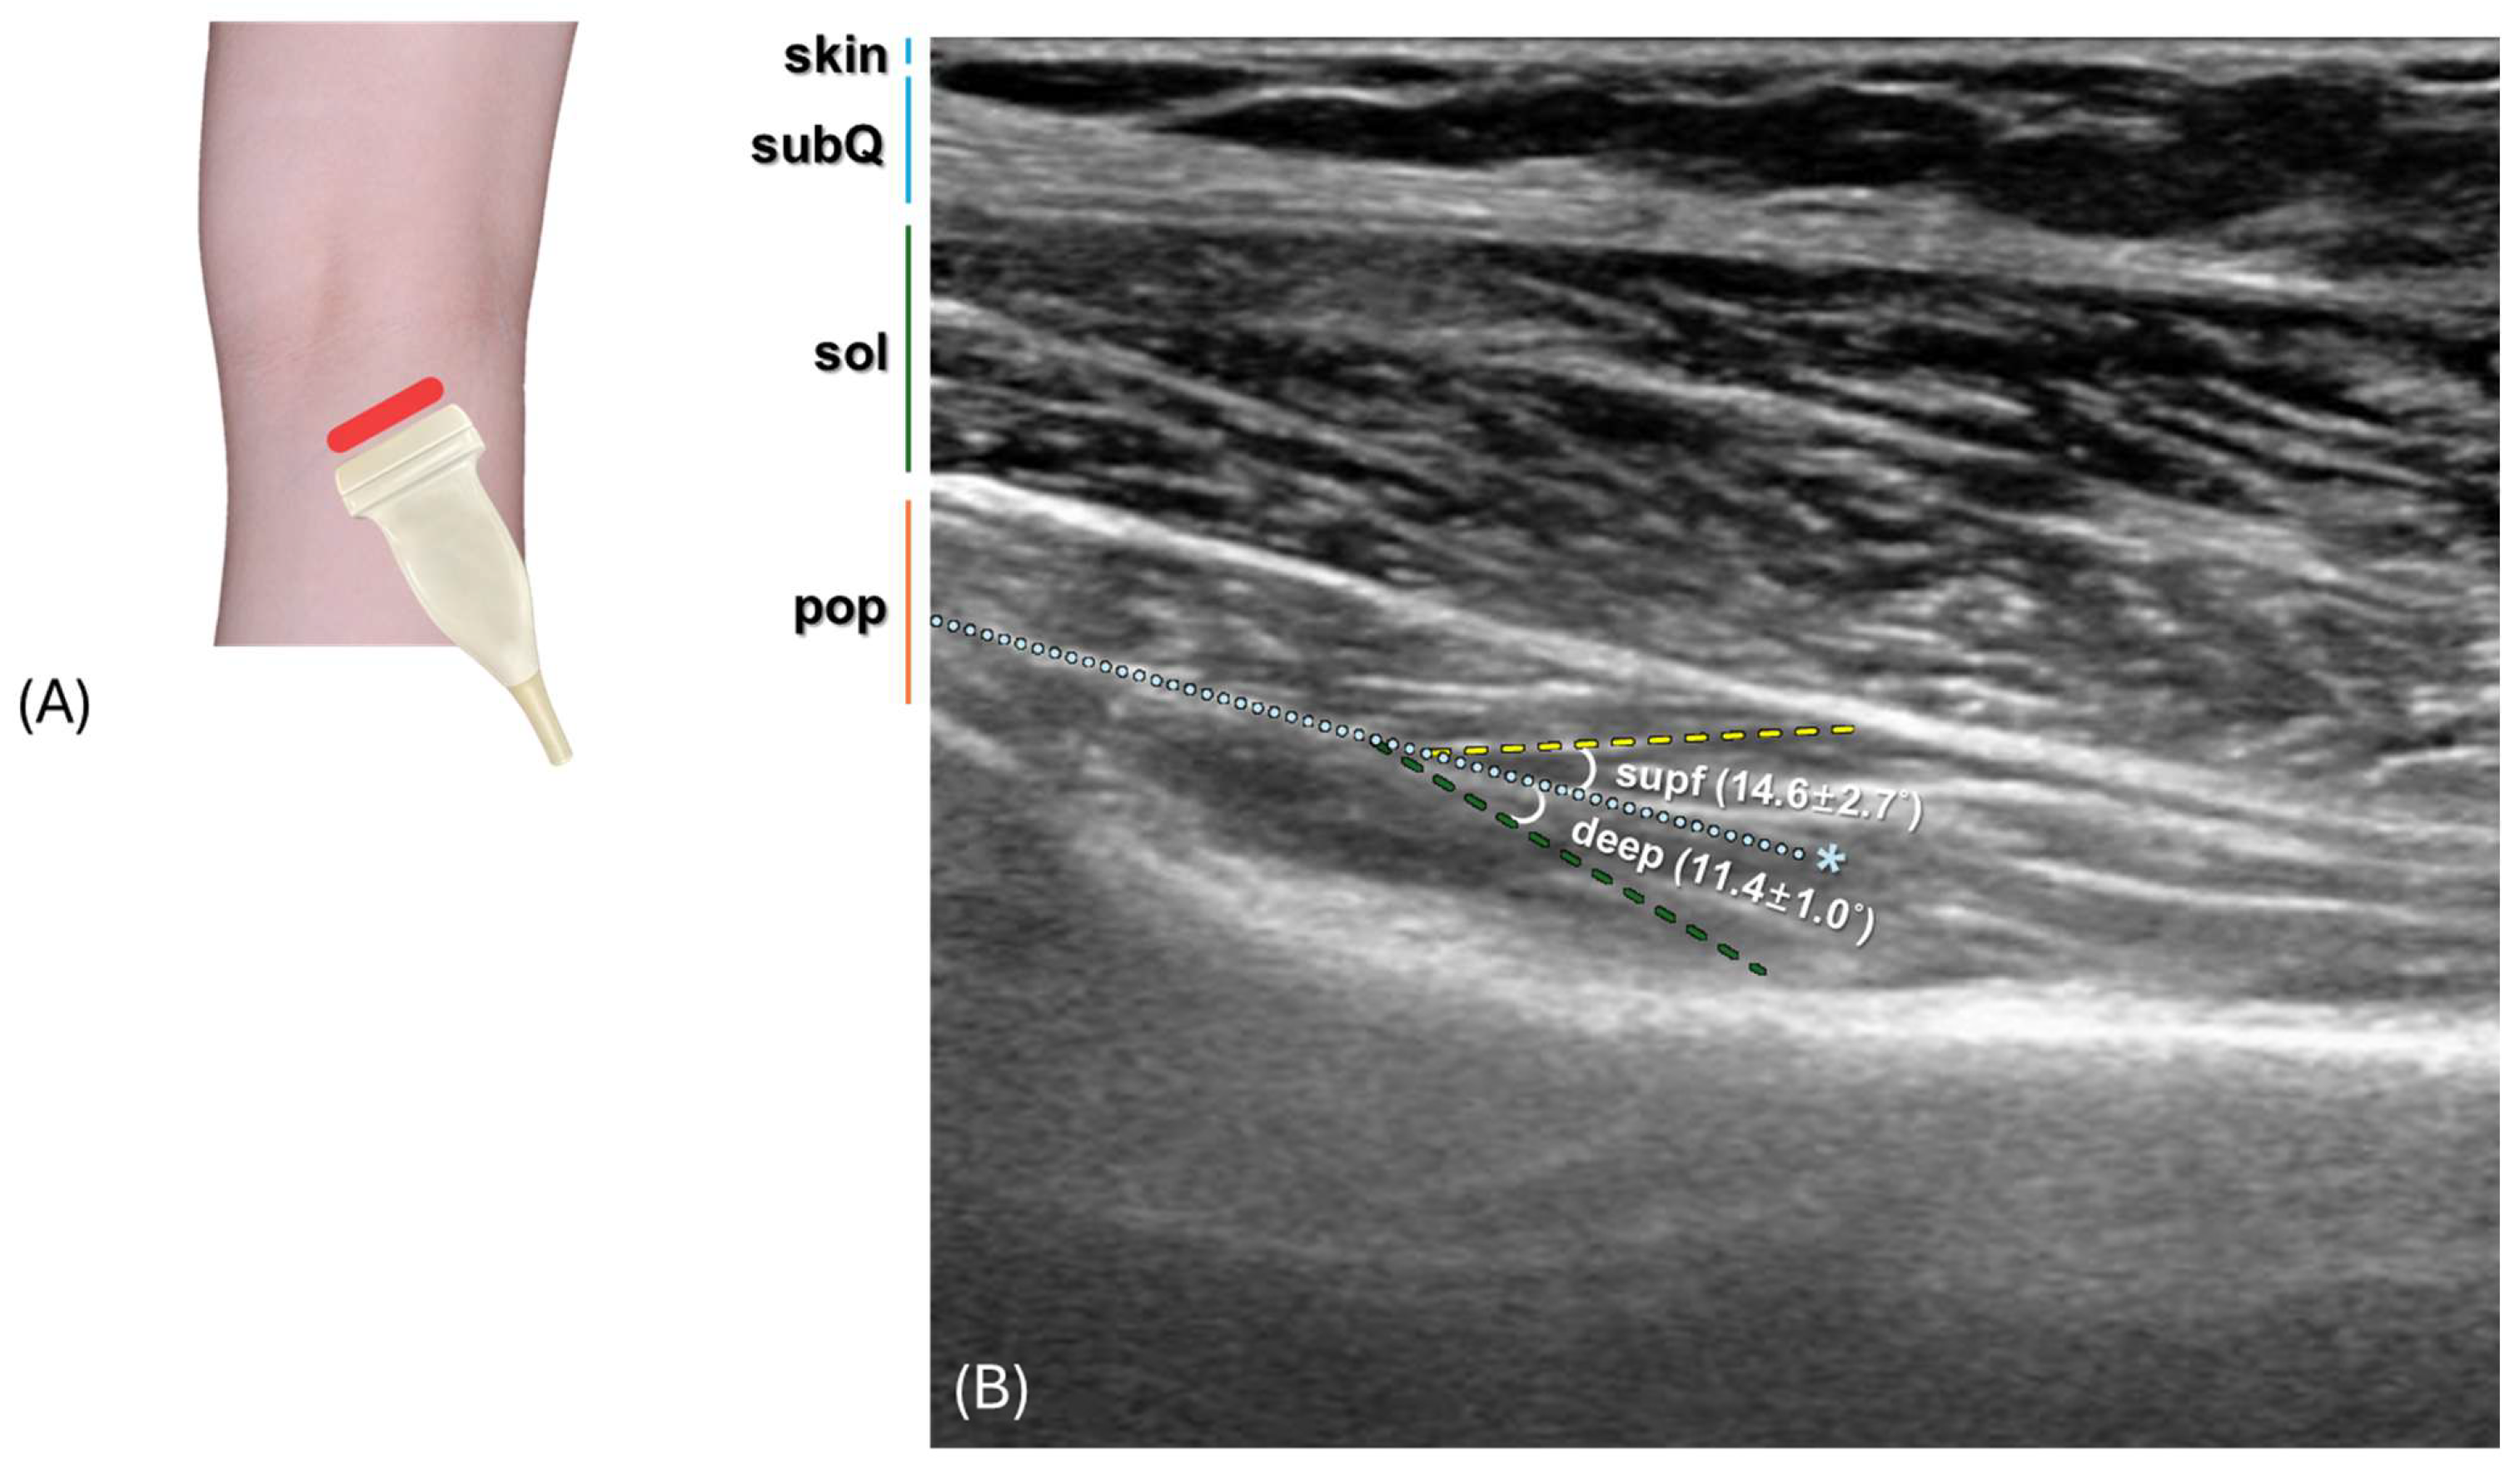

3.5. Ultrasound Scanning Analysis